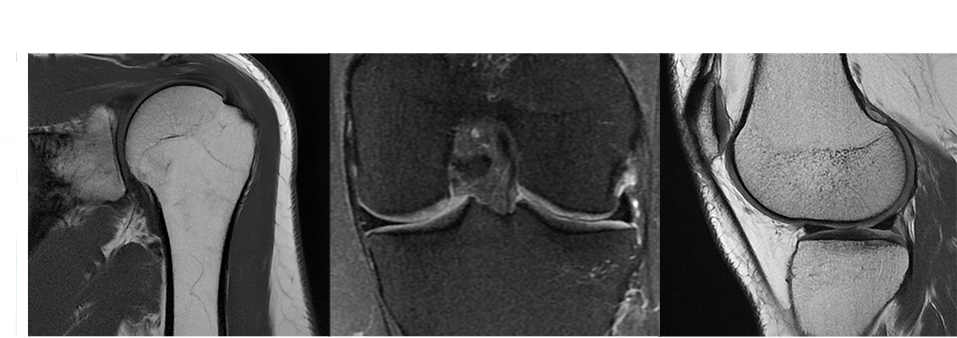

Bobinas de hombro y rodilla T/R de 16 canales

La bobina de hombro de 16 canales presenta un novedoso diseño de bobina adaptable a la anatomía que ofrece una mejora en el flujo de trabajo de posicionamiento más eficiente y una extraordinaria comodidad para el paciente. La flexibilidad de la parte anterior permite aproximarse más al paciente para conseguir la mejor relación señal-ruido e imágenes de la máxima calidad.

La bobina de rodilla de transmisión/recepción (T/R) de 16 canales ofrece imágenes de alta resolución de la rodilla. El diseño T/R proporciona un mayor rendimiento B1, con la posibilidad de conseguir resoluciones más altas, reducir el SAR y eliminar el efecto de solapamiento de las imágenes. Al disponer de mayor diámetro ofrece capacidad para una mayor diversidad de pacientes, permite preparar al paciente de una forma sencilla y aumenta su comodidad. El nuevo diseño es compatible con la aceleración de imágenes en todas las direcciones para obtener mejores resultados clínicos de forma más rápida.